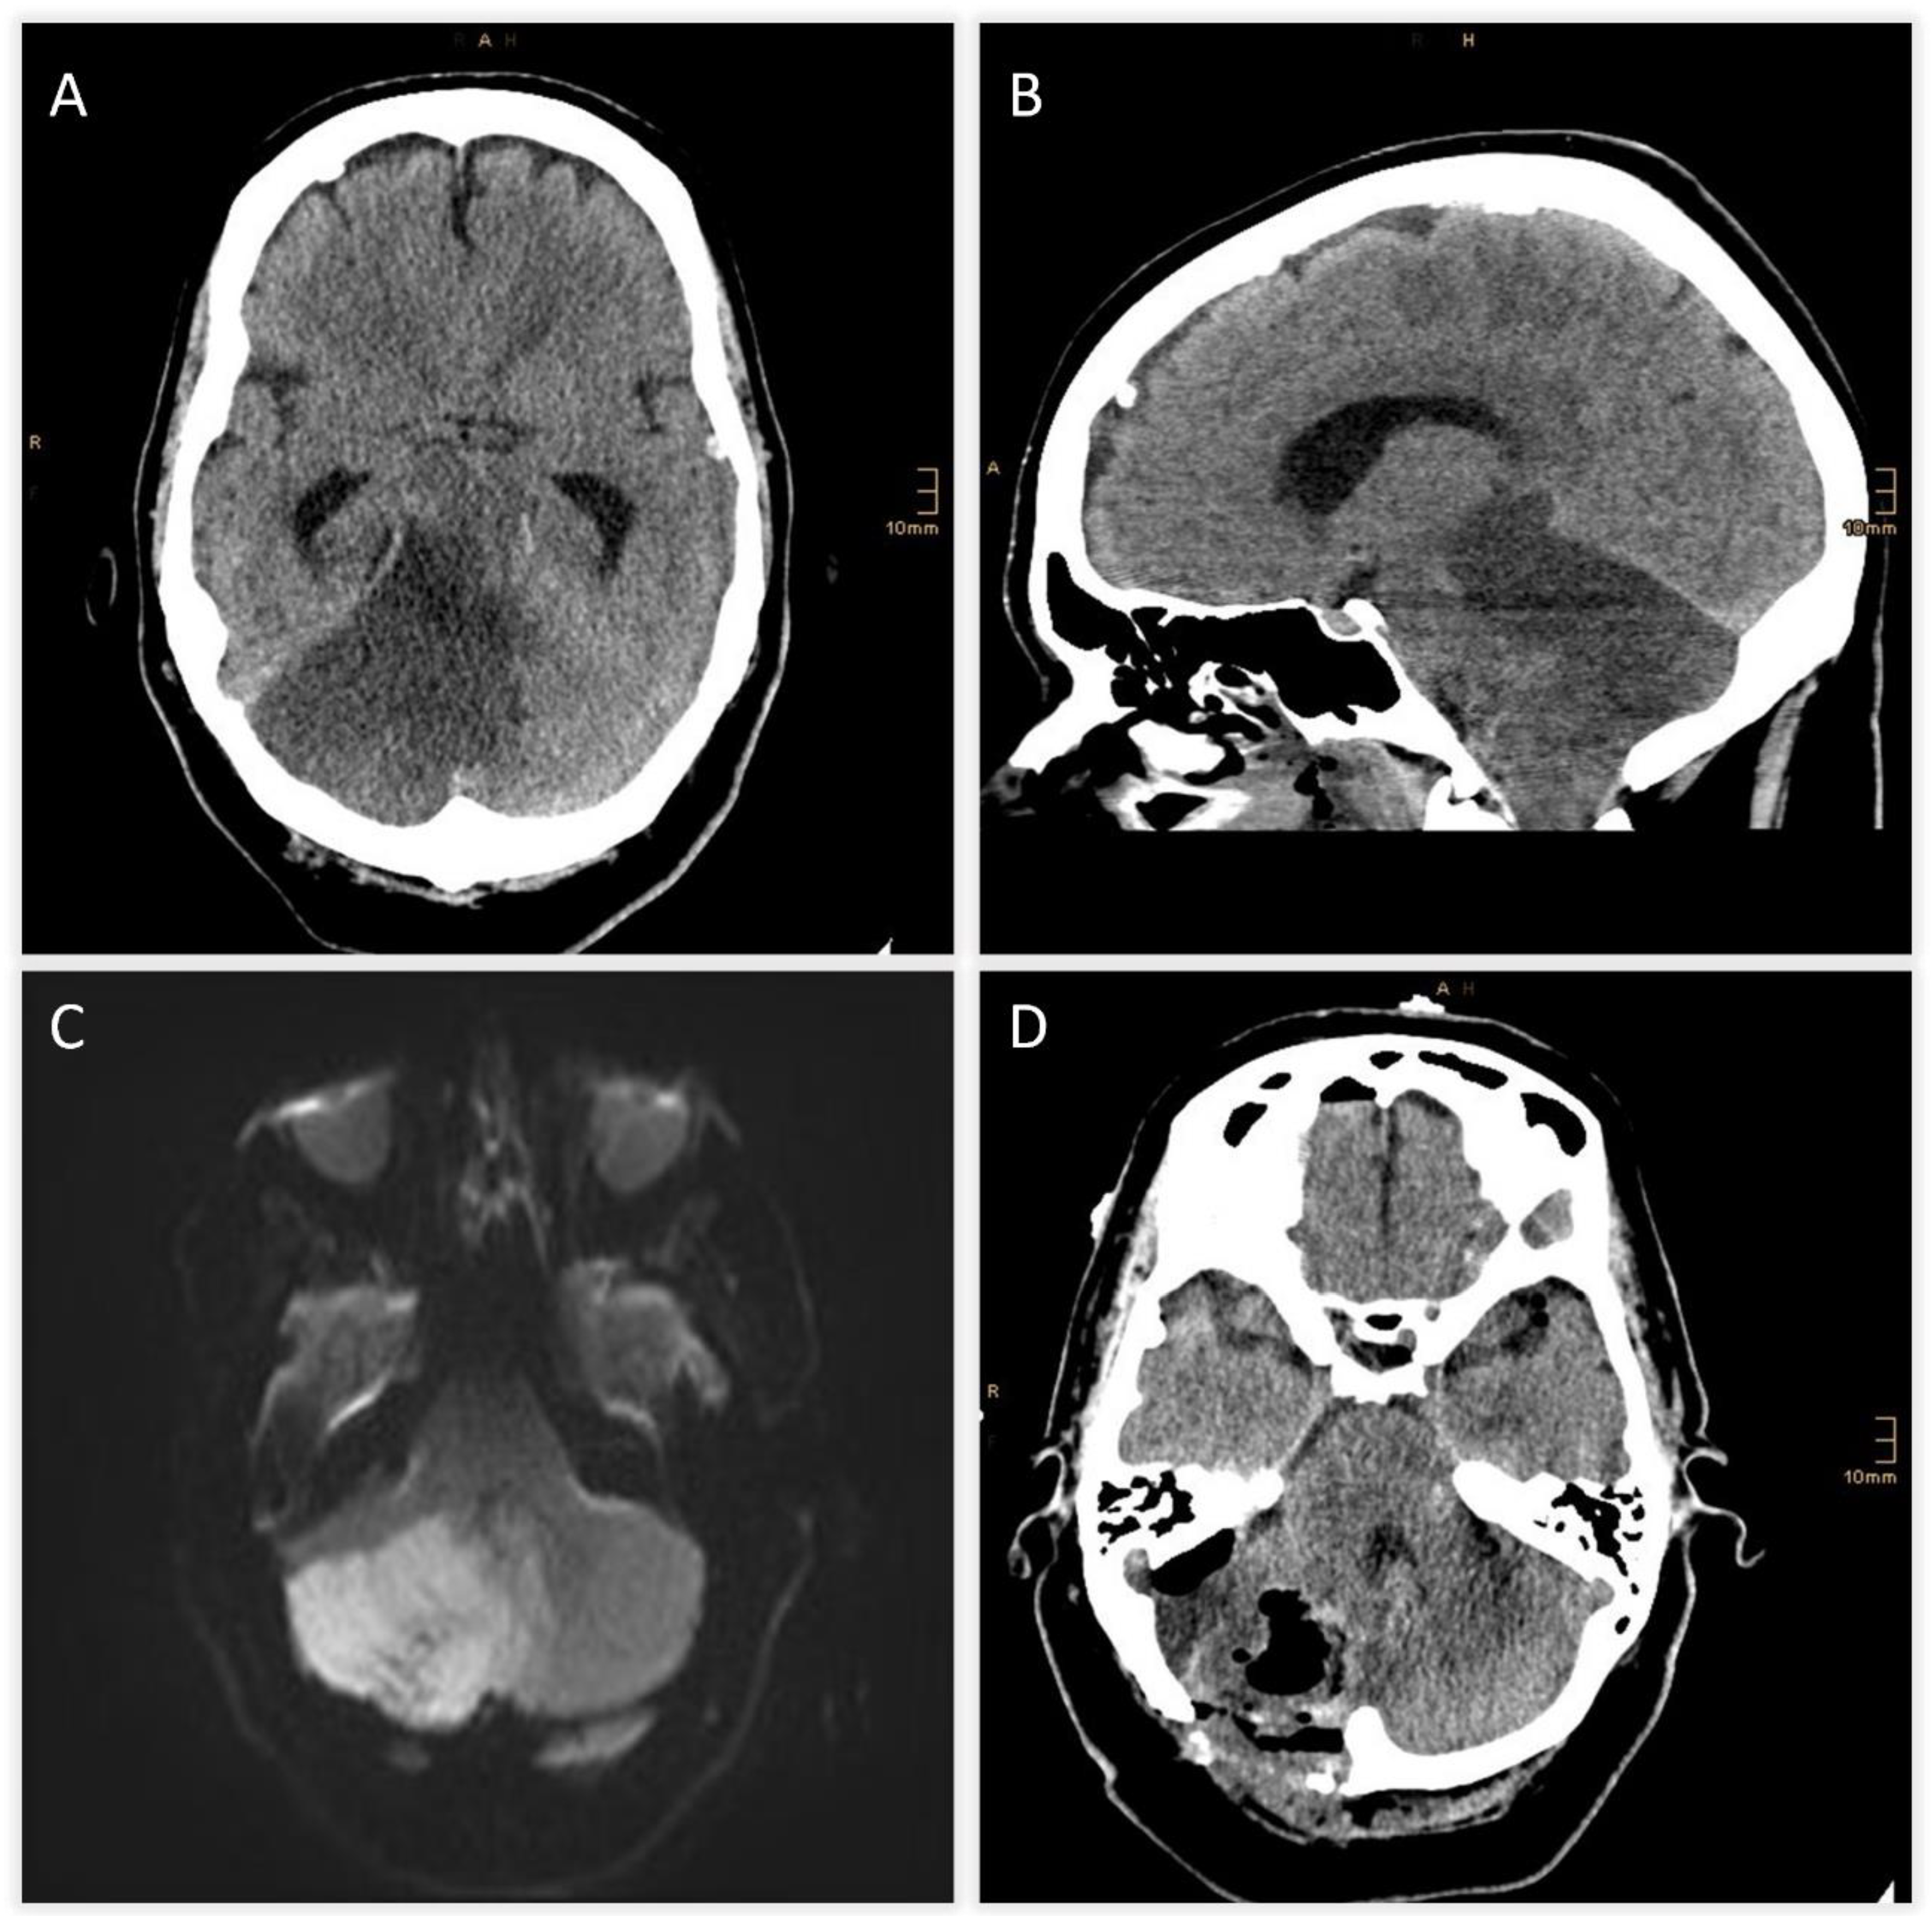

A 50-year-old woman with no prior medical history presented with acute severe vertigo, dysphagia, dysarthria, and diplopia. Neurological examination revealed skew deviation, left-sided hemihypesthesia, bilateral bradykinesia, and ataxia (NIHSS score 7). Initial diffusion-weighted MRI showed acute ischemia of the right cerebellum and vermis (Figure 1A).

TOF-angiography identified a thrombus at the basilar tip. Intravenous thrombolysis was administered, followed by DSA confirming right SCA occlusion with preserved basilar patency (Figure 1B). Mechanical thrombectomy was attempted but unsuccessful. Follow-up CT revealed extensive hypodensity in the right cerebellum with mass effect and apparent extension into the brainstem, raising concern for infarction and poor prognosis (Figure 2A and Figure 2B). Immediate MRI, however, excluded brainstem infarction and confirmed predominantly reversible edema (Figure 2C). Emergency suboccipital decompression, partial resection of infracted parenchyma and ventricular drainage were performed (Figure 2D).

Figure 1. Diffusion-weighted MRI on admission showing acute ischemic infarction of the right cerebellar hemisphere and vermis. B) DSA demonstrating occlusion of the right SCA with preserved patency of the basilar tip.